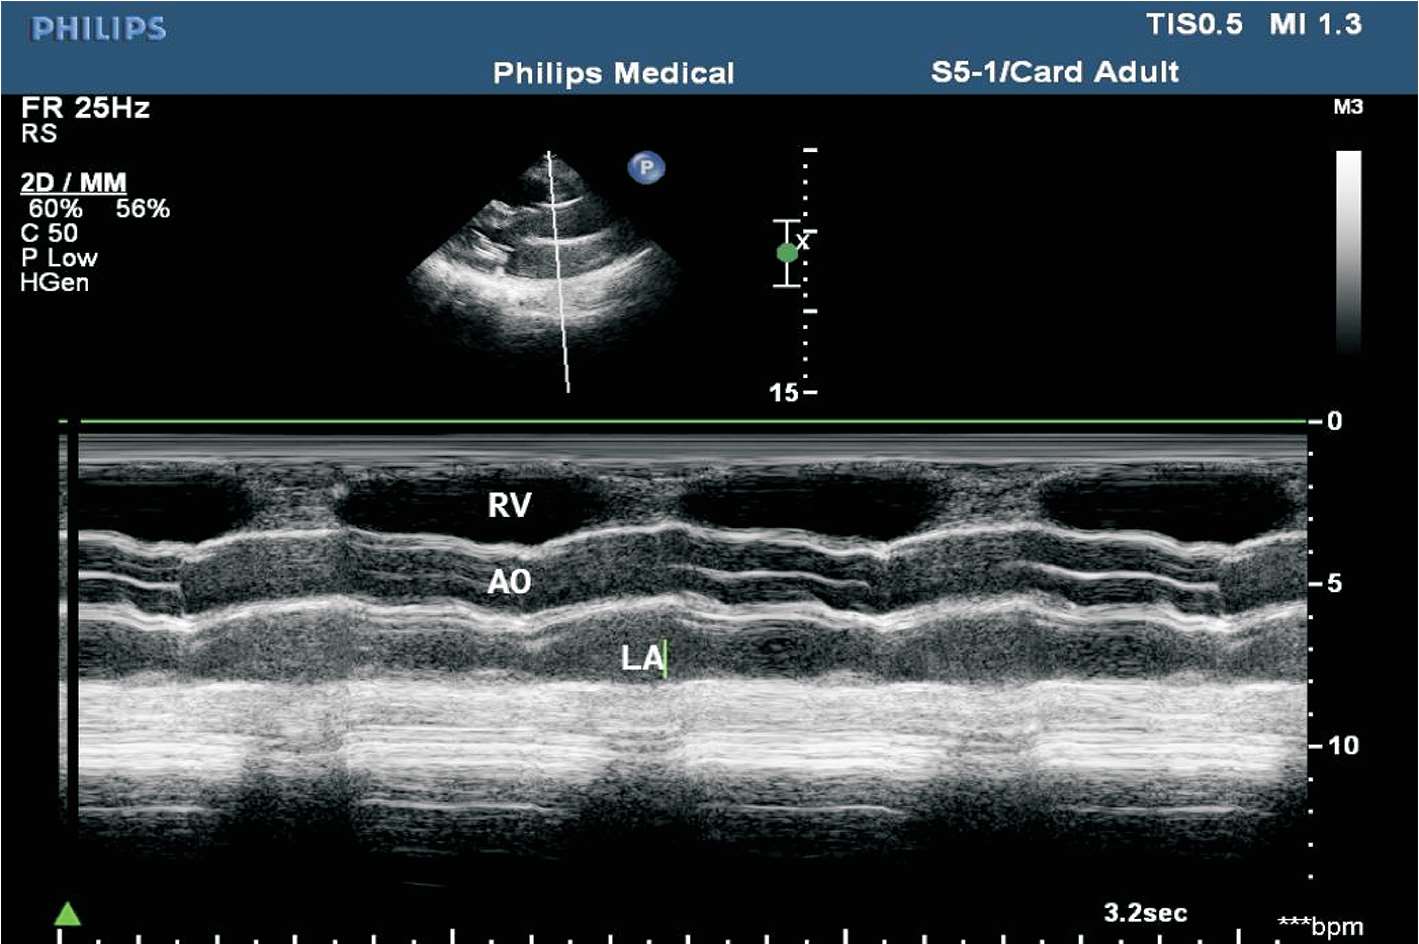

(1)胸骨旁左室长轴切面M型取样线置于主动脉瓣瓣尖水平。

(2)结构从前到后依次为右室流出道、主动脉、左心房等。其中右室流出道及主动脉根部内径于舒张末期测量,左心房前后径于收缩末期测量(见图1-21)。

图1-21 心底波群(RV:右心室;AO:主动脉;LA:左心房)